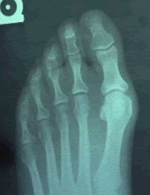

Bunion DeformityOne of the more common conditions treated by podiatric surgeons is the painful bunion, i.e. a painful bump on the inside and base of the big toe together with a crooked big toe. Patients with this condition will usually complain of pain when wearing certain shoes, especially snug fitting dress shoes, or with physical activity, such as walking or running. There are several surgical procedures to correct bunions. Selection of the most appropriate procedure for each patient requires a thorough examination of the patient and a review of weight-bearing x-rays of the foot. All surgical procedures require cutting and repositioning the first metatarsal, and sometimes the bones of the big toe itself.

The classic bunion, medically known as Hallux Abducto Valgus or HAV, is a bump on the side of the great toe joint. This bump represents a thickening of the joint tissues and the underlying bone on the inside of the metatarsal head, the bone that joins the big toe at its base. In addition, there is also deviation of the great toe toward the second toe. In severe cases, the great toe can either lie above or below the second toe. Shoes are often blamed for creating these problems. This, however, is inaccurate; In places where people do not wear shoes, the statistical chance of a crooked big toe is the same.

Bunions develop from abnormal foot structure and poor mechanics of the foot. This leads to stretching of supporting soft tissue structures such as joint capsules and ligaments with the end result being gradual deviation and dislocation of the big toe, which then pushes back against the 1st metatarsal head making it stick-out. As this deformity increases, there is an abnormal pull of certain tendons, which leads to the drifting of the great toe toward the 2nd toe more-and-more. This cycle continues until the big toe almost completely dislocates off of the 1st metatarsal head.